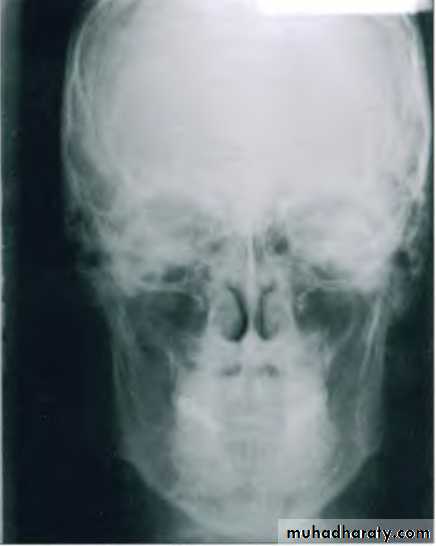

Posteroanterior (p-a) cephalometric radiograph

Image Receptor and Patient Placement:Image receptor is placed in front of the patient

The patient is placed so that the canthomeatal line is perpendicular to the image receptor

Uses :

Provides information related to skull widthSkull symmetry

Vertical proportions of skull, craniofacial complex & oral structuresFor assessing growth abnormalities & trauma